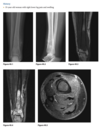

An anteroposterior view of the pelvis

shows flaring of the metaphyseal regions of

the proximal femurs and numerous osteochondromas

arising from the right iliac crest, pubic bones, and proximal right femur (arrows).

Axial CT through upper pelvis - Large right exostosis with soft tissue mass.

AP radiograph of knee - multiple osteochondromas arising from femur and fibula.

DIAGNOSIS: Multiple hereditary exostosis

AD disorder age 10-20s

Signs of malignant transformation - Growth of previous stable exostosis, new or increasing calcifications, new bony erosion

Associated with chondrosarcoma